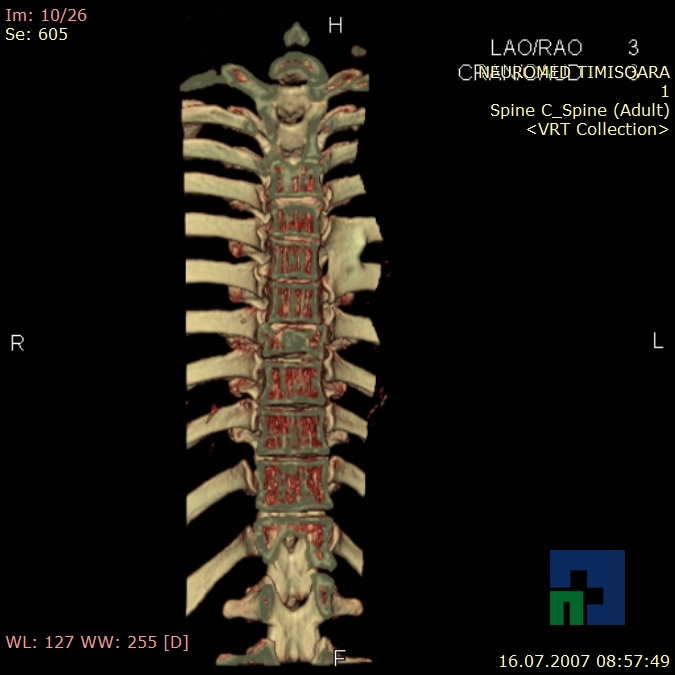

- Diagnosticul fracturilor:

- Unice

- Multiple

- Cu înfundare

- Complexe cranio-sinusale

- Complexe cranio-etmoidale

- Complexe cranio-orbitare

- Complexe cranio-faciale